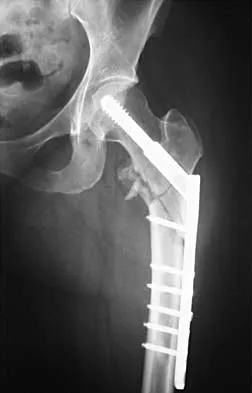

Figures 22a and 22b show the radiographs of a patient who reports stiffness of the hip and associated pain. Management should consist of

The patient has grade IV heterotopic ossification with the limb in an abnormal nonfunctional position. Treatment should consist of excision of the bone to restore hip motion and prophylaxis to prevent recurrent formation. The best time to excise the bone is controversial, with no conclusive evidence supporting early or late excision. Pellegrini VD Jr, Koniski AA, Gastel JA, Rubin P, Evarts CM: Prevention of heterotopic ossification with irradiation after total hip arthroplasty: Radiation therapy with a single dose of eight hundred centigray administered to a limited field. J Bone Joint Surg Am 1992;74:186-200.

- Warren SB, Brooker AF Jr: Excision of heterotopic bone followed by irradiation after total hip arthroplasty. J Bone Joint Surg Am 1992;74:201-210.